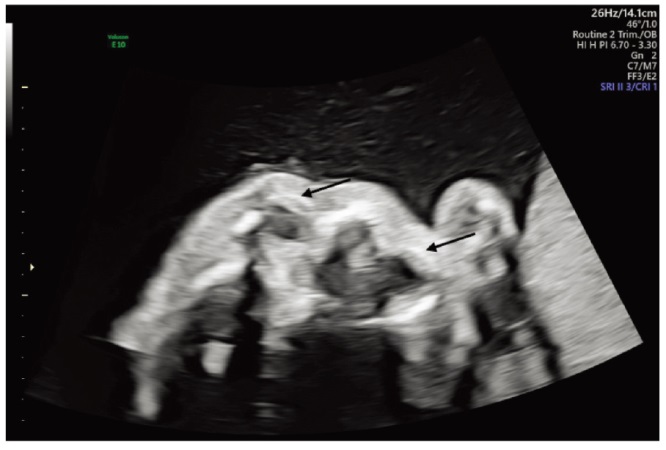

Burrill N, Khalek N, Oliver ER, et al. Case report of fetus with Lowe syndrome: Expanding the prenatal phenotype[J]. Prenat Diagn, 2024, 44(5):665-668. doi: 10.1002/pd.6563.